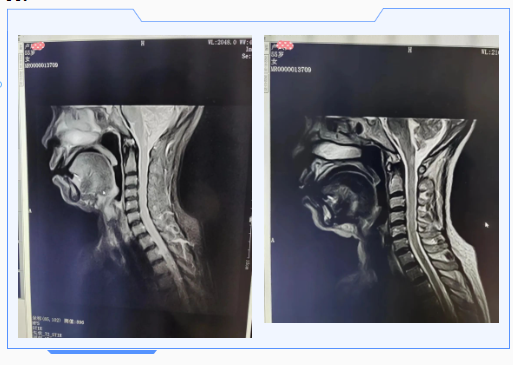

于是,卢X在家属的陪同下来到阳光医院,神经内科主任那彦华为卢X进行了详细查体,初步将病因定位在颈髓,遂后针对该部位进行了检查:颈椎核磁显示颈髓片状异常信号,腰穿脑脊液细胞数偏高。结合患者一个月前带状疱疹病毒感染史,那主任诊断卢X患有颈髓脱髓鞘病变。